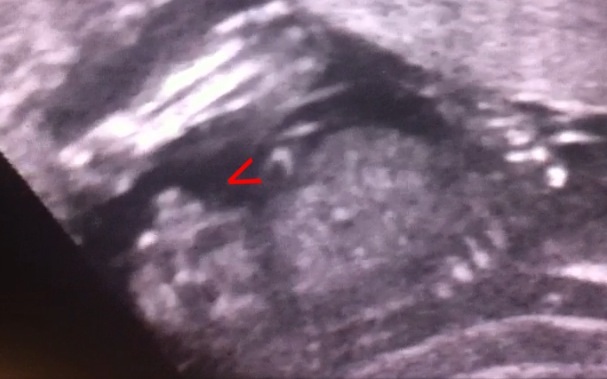

Maybe a boy nub!What gestation?

I see the leg and knees so its possible that it is a boy nub but I cant be sure without gestation.

Attachment 25363Sorry lol I will label the picture for you. I can see how you are having trouble. Sorry here.

17 weeks and thanks for looking ladies